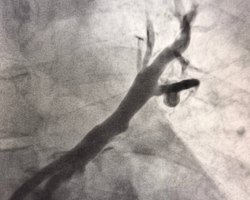

Вмешательство проводилось через бедренный венозный доступ под местной анестезией. Основная сложность операции заключалась в полной окклюзии обеих легочных вен и необходимости точной навигации инструментов в условиях ограниченной визуализации. После реканализации поражённых участков были имплантированы стенты, обеспечившие надёжное восстановление просвета сосудов и полноценный венозный отток из лёгких.

В результате кровоток по левой верхней и левой нижней легочным венам полностью восстановлен. Состояние пациента стабилизировалось, одышка регрессировала. В настоящее время пациент чувствует себя хорошо.